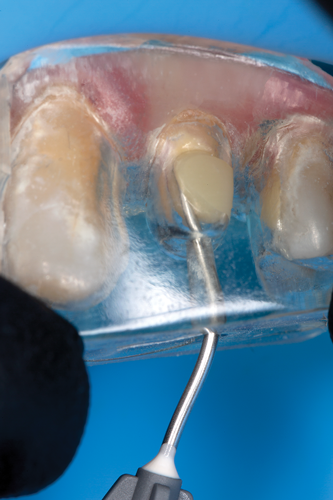

The clear silicone matrix was placed over the posterior segment of the maxillary arch, and an opacious A2-shaded injectable flowable universal resin composite was injected through a small opening above the preparation and fiber post (Figure 20 and Figure 21). The resin composite was cured through the clear resin matrix on the incisal, facial, and lingual aspects for 40 seconds each. Upon removal of the matrix, the excess polymerized composite resin was removed with a #12 scalpel blade, and the incisal sprue was removed using a tapered diamond finishing bur. A round, tapered diamond bur was used to establish the gingival margin (Figure 22) and a needle-shaped finishing bur was used to complete the finishing of the preparation.

Fig 20. The clear silicone matrix was placed over the posterior segment of the maxillary arch, and flowable resin composite was injected through a small opening above the preparation and fiber post.

Figure 20

Fig 21. During the injection process, the tip was removed slowly while injecting to prevent the incorporation of air bubbles.

Figure 21